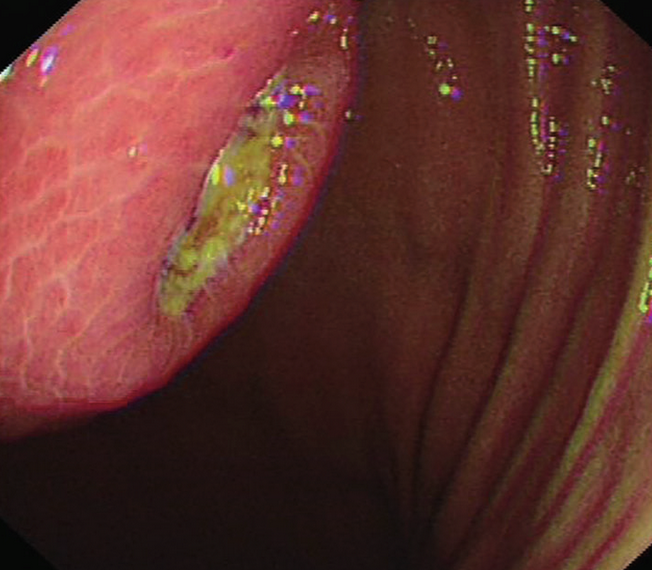

Extreme stenosis of the involved transverse colon . Residual seeds were unable to overcome the stenotic segment (Courtesy Dr. V. Penopoulos)